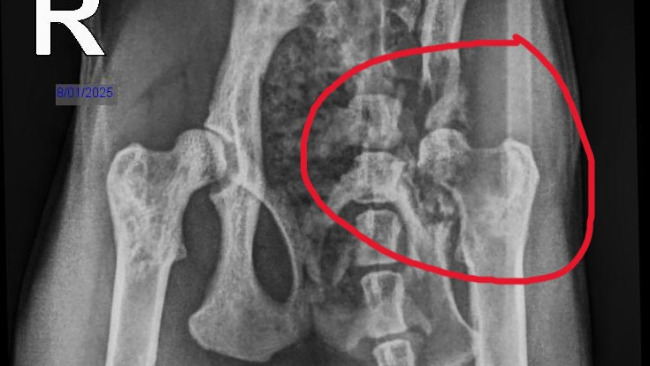

Problem z prawą łapką okazał się bardzo poważny - pręt który stabilizował jej kość pękł w pół, a sama kość została zmiażdżona. Nie wiemy jak do tego doszło, ale to prawdopodobnie przez to, że kręciła się po domu i gdzieś utknęła.

Miała również przepuklinę.

Rokowanie było takie, że nawet przy wyleczeniu problemów neurologicznych, potrzebna byłaby jej amputacja prawej przedniej i tylnej lewej łapki, co byłoby ciężkim życiem dla kota. Dodatkowo była w ogromnym bólu i cierpiała, więc podjęliśmy taką decyzję, żeby już się nie męczyła.